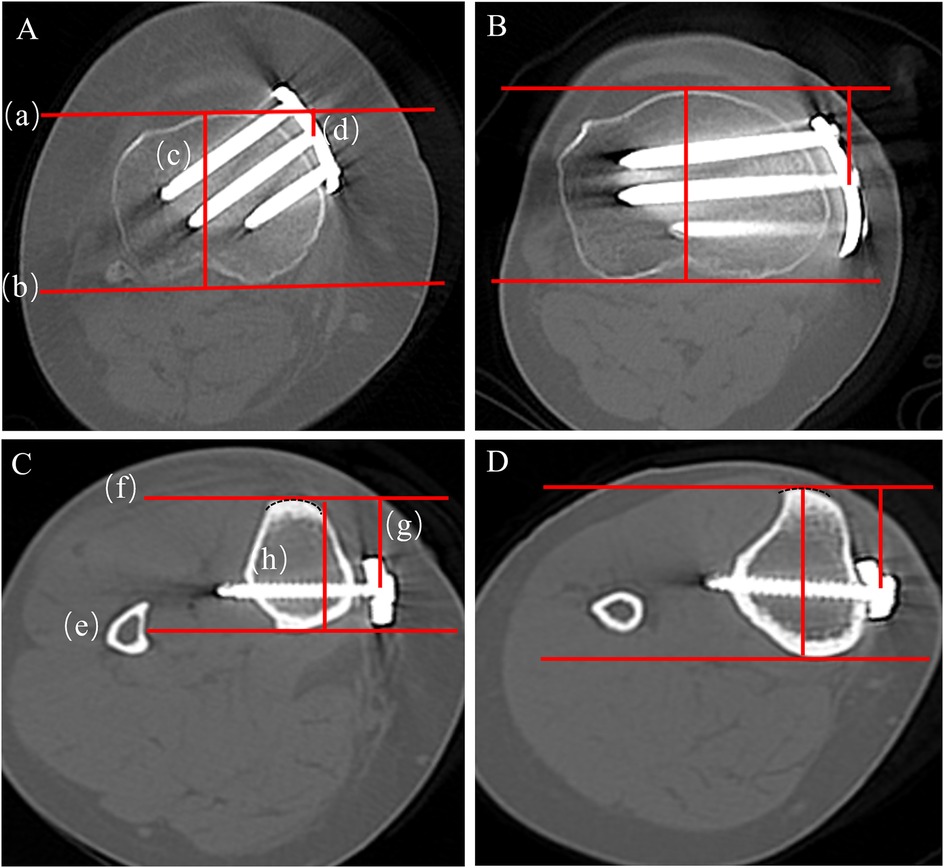

Background: High tibial osteotomy (HTO) corrects varus malalignment and unloads the medial knee compartment, yet the conventional T-shaped locking plate may cause discomfort due to suboptimal anatomic conformity. We developed a novel locking plate to improve anatomic fit and fixation stability and compared it with the T-shaped plate in Anterior Popliteus Transtibial-tuberosity high tibial osteotomy (APTT-HTO). Methods: This single-center retrospective observational comparative study included 14 consecutive patients who underwent APTT-HTO between August 2024 and June 2025. Patients were grouped by implant type (novel plate: n = 7; T-shaped plate: n = 7). Postoperative CT quantified plate orientation/position, plate–bone conformity (gap and position mismatch), screw alignment, and standard alignment parameters (hip–knee– ankle angle [HKA], posterior tibial slope [PTS]). Results: The novel plate showed more posteromedial placement and superior anatomic conformity. The plate angle relative to the posterior tibial condylar reference line was larger with the novel plate (74.49° ± 8.76°) than with the T-shaped plate (62.62° ± 7.05°, P<0.05). The proximal central screw–plate angle was smaller (5.70° ± 4.80° vs 27.48° ± 6.05°, P<0.05), the plate–bone gap was reduced (1.84 ± 0.68 mm vs 2.98 ± 0.38 mm, P<0.05), and plate position mismatch was lower (20.20% ± 7.70% vs 37.70% ± 10.00%, P<0.05). Proximal and distal offsets considered separately were not significantly different (P>0.05). Both groups achieved the planned coronal correction, and sagittal PTS remained stable (P>0.05). Conclusions: In this CT-based cohort, the novel anatomically contoured locking plate achieved superior anatomic conformity in APTT-HTO—characterized by more posteromedial positioning, a more favorable screw trajectory, and improved plate–bone apposition—compared with a conventional T-shaped plate. These findings warrant confirmation in larger, prospective studies.